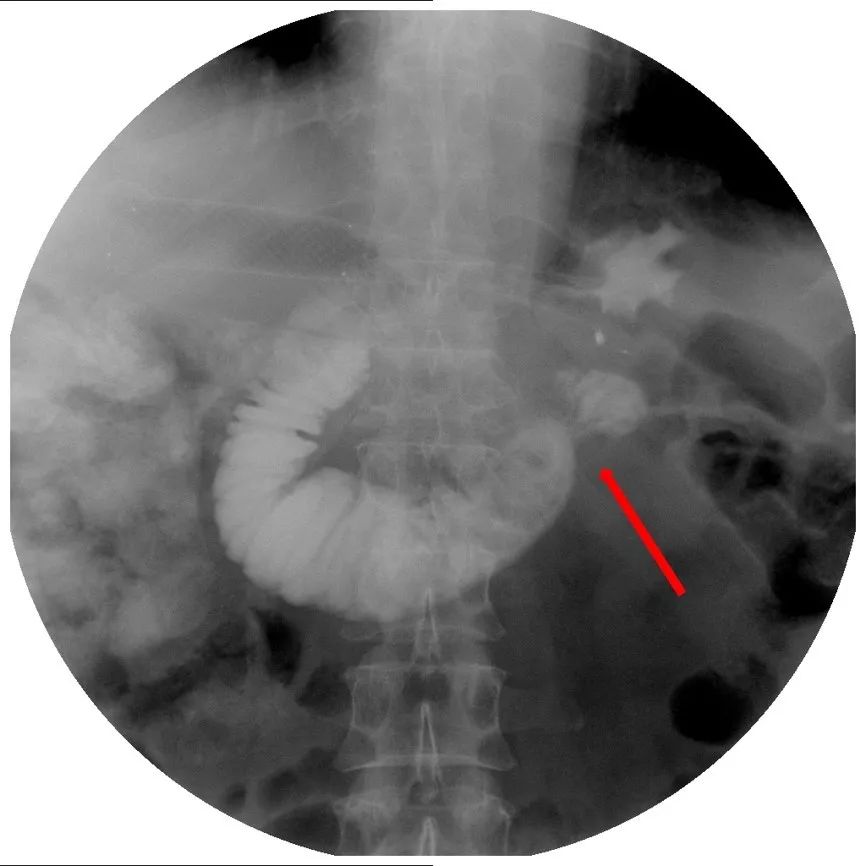

2018年8月底,患者再次出现恶心、呕吐症状。无明显的腹痛症状,无发热。上消化道碘油造影见近端小肠扩张,造影剂通过受阻(图7、图8)。

图7 上消化道造影见近端小肠局部明显扩张

图8 消化道造影见扩张的小肠段远端有局限的狭窄,造影剂通过不畅